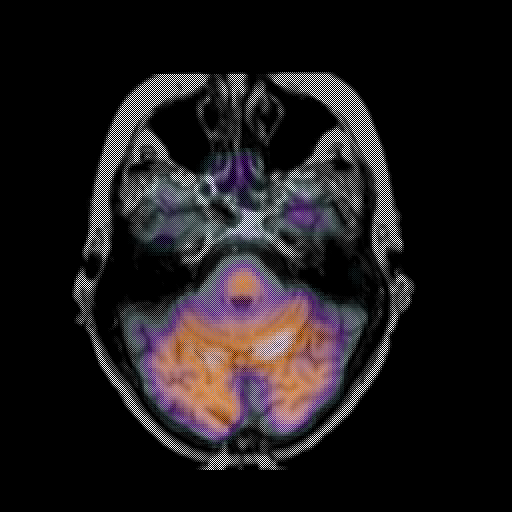

overlay: Slice 15

Slice 15

MRCBFCBF with

T1PDT2T1PDT2